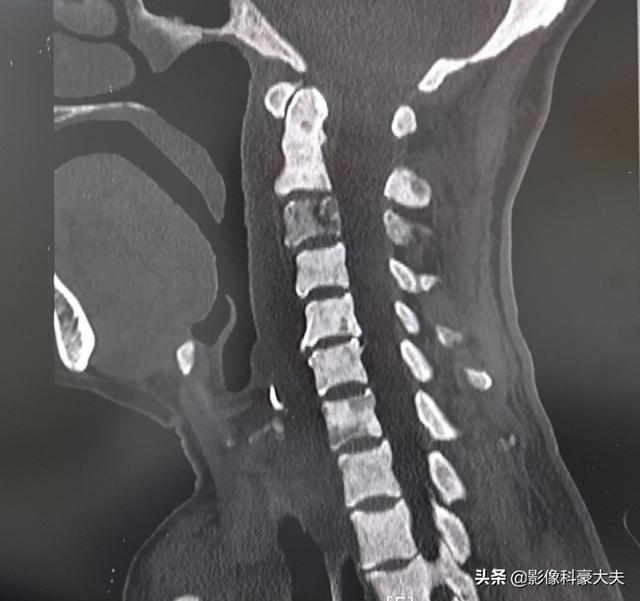

Il s'agit d'un patient atteint d'un cancer gastrique. Le vieil homme a déclaré que son cou était un peu douloureux avant l'opération et que, par conséquent, le scanner cervical a révélé d'importantes métastases dans la colonne cervicale, qui ne pouvait plus faire l'objet d'une opération.

Si seules des métastases osseuses apparaissent et que la lésion primaire est bien contrôlée, une survie à long terme est souvent possible, car les métastases osseuses ne sont généralement pas fatales.